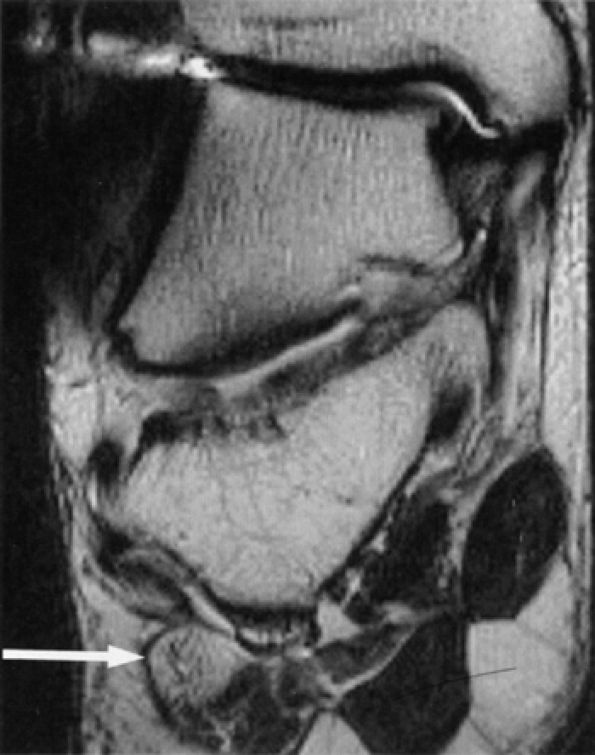

FIGURE 6.49 ● Tarsal tunnel syndrome and medial plantar nerve denervation edema due to proliferative synovitis. (A) Axial T2-weighted image demonstrates a synovial mass (asterisk) in the tarsal tunnel. (B) Sagittal T2-weighted fat-suppressed image illustrates denervation edema in the flexor digitorum brevis muscle (asterisk). Note associated osteoarthritic changes in the anterior tibiotalar joint (arrow).

|